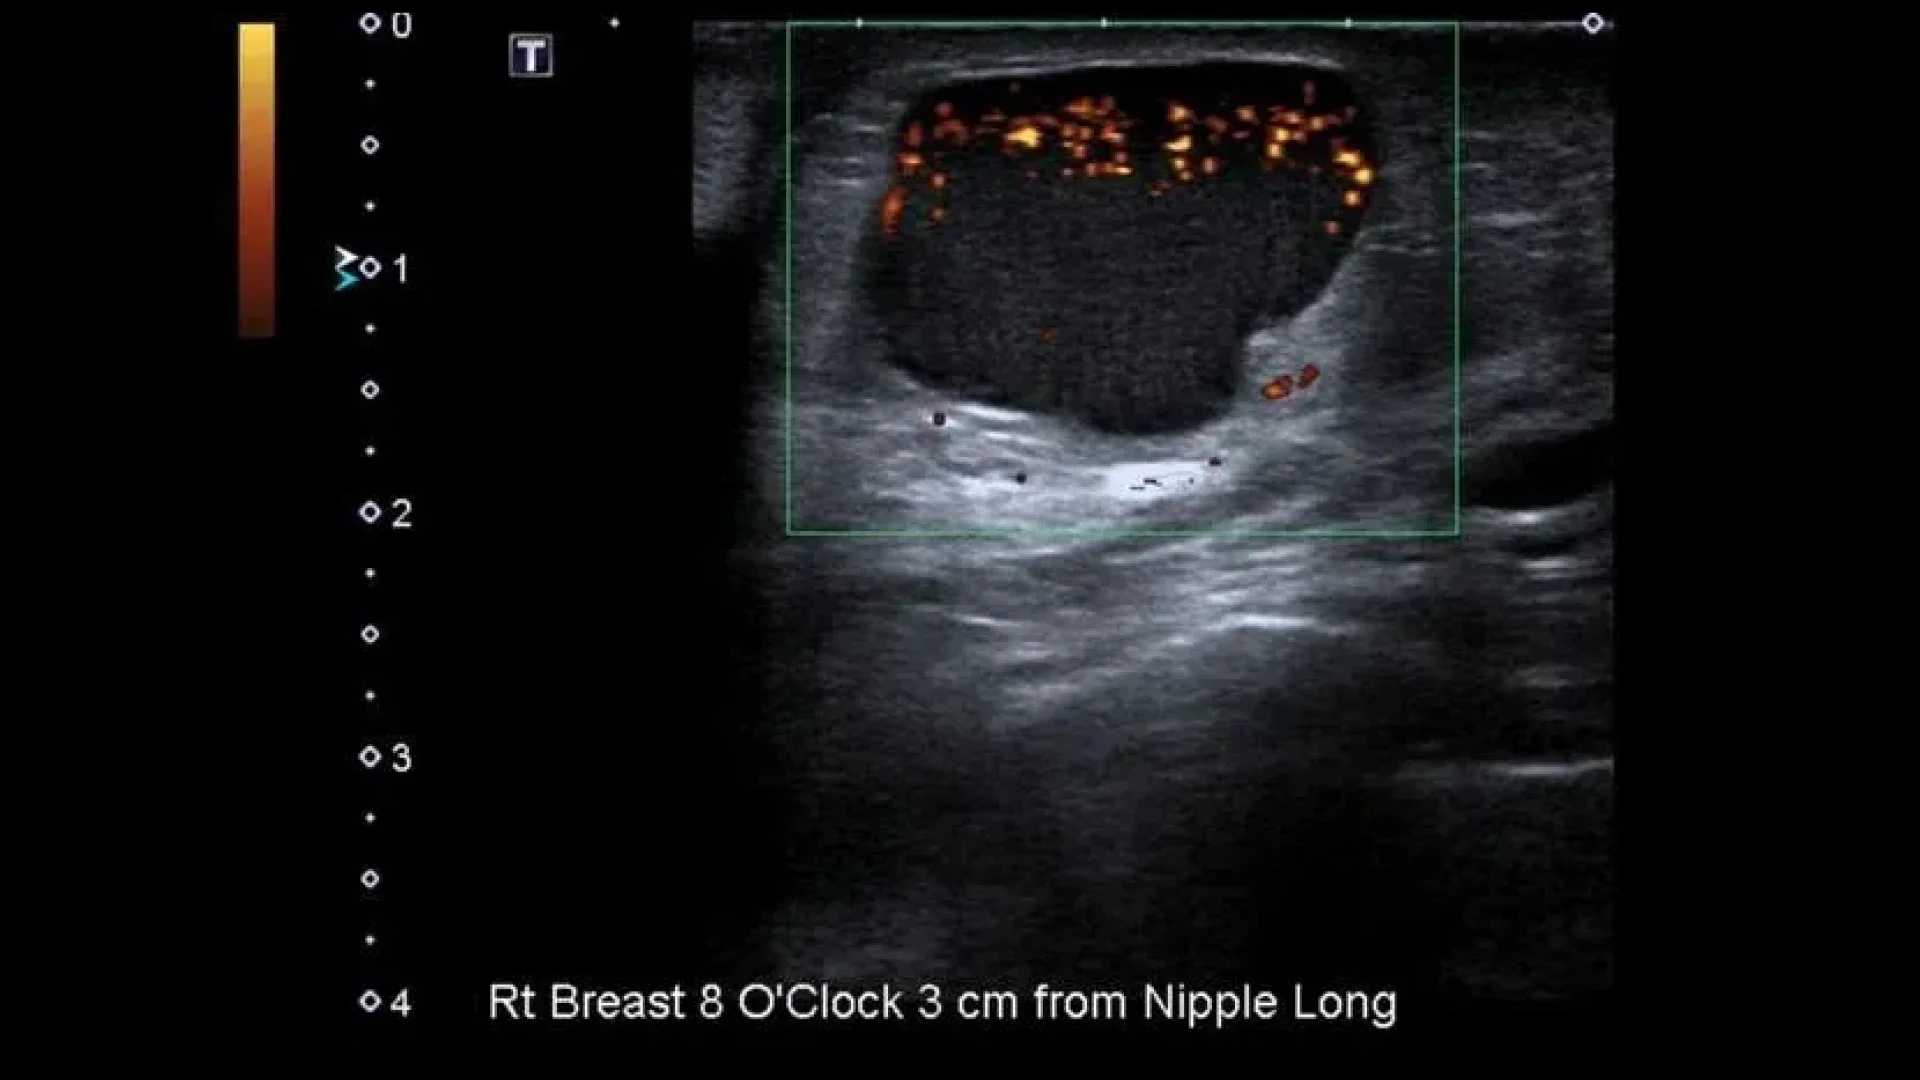

Ultrasound with Doppler ultrasonography of a simple large breast cyst

Ultrasound with Doppler ultrasonography of a simple large breast cyst. Author: Henry Knipe. Source: Radiopaedia. Simple Breast Cyst [12]

Simple breast cysts are characterized by the following ultrasound signs:

• The horizontal dimension is larger than the vertical dimension;

• The mass is non-echoic and homogeneous;

• The walls are hyperechoic, thin and smooth;

• Dorsal signal amplification;

• Lack of blood flow within the mass.